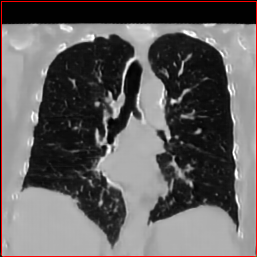

HA-GAN (Sun et al. 2022)

GenerateCT (Hamamci et al. 2024)

MedSyn (Xu et al. 2024)

MAISI-DDPM (Guo et al. 2025)

MAISI-v2

Figure 2: Qualitative comparison across axial (top row), sagittal (middle row), and coronal (bottom row) views. Columns correspond to different methods. MAISI-DDPM and MAISI-v2 in this figure are unconditional synthesis which do not use ControlNet or segmentation maps.

Qualitative Evaluation:

Figure 2 presents representative slices from the axial, sagittal, and coronal planes. GenerateCT (Hamamci et al. 2024) is a 2D model, so it lacks inter-slice consistency, leading to poor image quality in the sagittal and coronal views. MedSyn (Xu et al. 2024) produces noticeably blurry results with mosaic-like artifacts, such as region inside the red box. HA-GAN (Sun et al. 2022) generates visually sharp images but with mosaic-like artifacts, such as region inside the red box. Also, its voxel spacing is not available, which limits its applicability in real-world medical imaging tasks. Moreover, all three methods are restricted to synthesizing small anatomical regions. In contrast, both MAISI and MAISI-v2 are capable of generating high-quality 3D volumes that span larger body regions while preserving fine anatomical details and realistic structure.